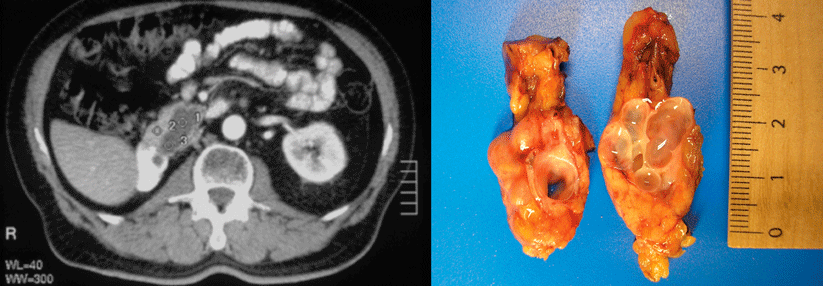

In einer Studie mit transgenen Mäusen entwickelten die Tiere, die CA19-9 exprimierten, eine schnell fortschreitende und schwere Pankreatitis. Waren die Nager zusätzlich Träger des KRAS-Onkogens, erkrankten sie im Verlauf an einer aggressiven Form von Bauchspeicheldrüsenkrebs.

Diese Ergebnisse weisen darauf hin, dass CA19-9 in der Ätiologie von Pankreatitiden und Pankreas­karzinomen eine bedeutende Rolle spielt, folgern Professor Dr. Dannielle­ D. Engle­ vom Cold Spring Harbor Laboratory und dem Lustgarten Foundation Pancreatic Cancer Research Laboratory und ihre Kollegen.